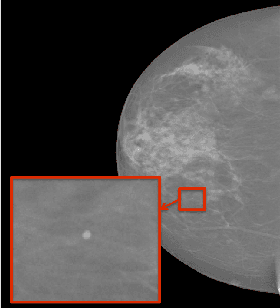

Abstract:In mammography, the efficacy of computer-aided detection methods depends, in part, on the robust localisation of micro-calcifications ($\mu$C). Currently, the most effective methods are based on three steps: 1) detection of individual $\mu$C candidates, 2) clustering of individual $\mu$C candidates, and 3) classification of $\mu$C clusters. Where the second step is motivated both to reduce the number of false positive detections from the first step and on the evidence that malignancy depends on a relatively large number of $\mu$C detections within a certain area. In this paper, we propose a novel approach to $\mu$C detection, consisting of the detection \emph{and} classification of individual $\mu$C candidates, using shape and appearance features, using a cascade of boosting classifiers. The final step in our approach then clusters the remaining individual $\mu$C candidates. The main advantage of this approach lies in its ability to reject a significant number of false positive $\mu$C candidates compared to previously proposed methods. Specifically, on the INbreast dataset, we show that our approach has a true positive rate (TPR) for individual $\mu$Cs of 40\% at one false positive per image (FPI) and a TPR of 80\% at 10 FPI. These results are significantly more accurate than the current state of the art, which has a TPR of less than 1\% at one FPI and a TPR of 10\% at 10 FPI. Our results are competitive with the state of the art at the subsequent stage of detecting clusters of $\mu$Cs.